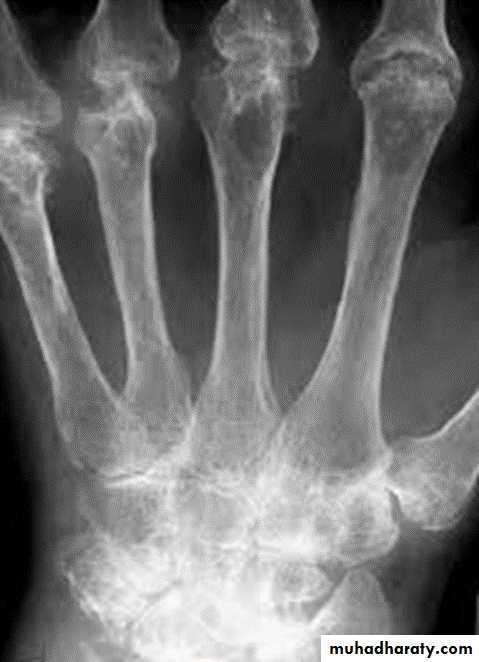

Rheumatoid arthritis. Bilateral changes are fairly symmetrical. Soft-tissue swelling is demonstrated, especially over the ulnar styloids. Erosions are demonstrated at the carpus, distal radius and ulna, with joint space narrowing and collapse of bone. Metacarpophalangeal erosions are also seen associated with joint space narrowing. There is a swan-neck deformity of the right fifth distal interphalangeal joint